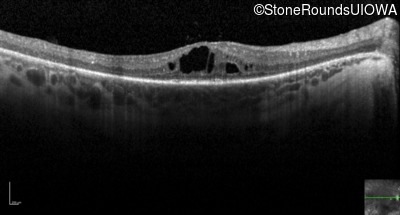

Optical Coherence Tomography - Right - 20/80 +2

Exemplar / OCT Stack